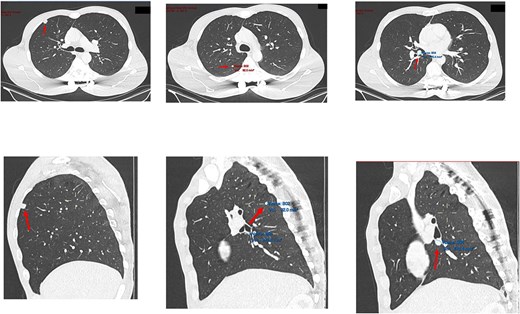

Subsequent computed tomography (CT) scan and positron emission tomography (PET) scan (Figs 2 and 3) confirmed the presence of three nodules in the right lung, suspicious for sarcoma metastases. An anterior, pleural-based upper lobe lesion, a posterior lower lobe lesion, and a lesion located at the bifurcation of his right middle and lower lobes.

Transverse and saggital views of the three nodules identified on an investigative CT scan.

The pleural-based anterior right lobe lesion showed fluorodeoxyglucose uptake on a PET scan.